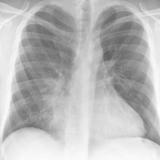

Case 1 PA

Date: 02/28/2004

Views: 3462